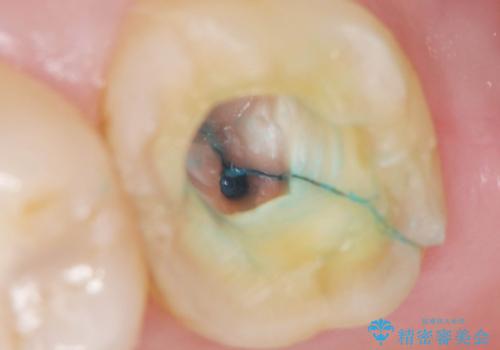

根分岐部病変とは、歯周病が進行して歯の周りの骨が吸収し歯の股の部分(根分岐部)まで組織破壊が達した状態です。

根分岐部は複雑な形態で歯ブラシがしづらく、手術をしてもなかなか全ての汚れを取り切るのが難しい部分です。

今回分岐部の状態を診査したところ、最も予後の悪い外側と内側が繋がっている状態(分岐部病変Ⅲ度)でした。

手術にて可及的掻爬を行い、経過観察を続けていましたが進行性の骨吸収を認めたためやむなく抜歯を行いインプラントを用いてかみ合わせの回復を行いました。